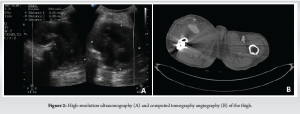

The patient underwent closed reduction and internal fixation with short proximal femoral nail anti-rotation (PFNA-2). Intraoperatively, the reduction was achieved by manipulation of the flexed and adducted proximal fragment with the help of a bone lever (Fig. 1). Intraoperative and post-operative periods were uneventful. The patient was discharged on post-operative day 6, the surgical wound healed, sutures were removed on post-operative day 15, and the patient was mobilized with partial weight bearing with walker support. The patient presented to us again on post-operative day 21 with complaints of pain and swelling over the right thigh. There was no history of fever or re-trauma, and the patient was able to walk full weight bearing with walker support. There was a pitting type of edema in his right lower limb extending up to the right proximal thigh. There was diffuse fullness over the anterior aspect of the thigh, which was more prominent on quadriceps contraction. All the peripheral pulses were well felt, there was no calf tenderness, and no neurological deficits. High-resolution ultrasonography showed a well-defined hetero-echoic collection in the proximal thigh in anterior and medial aspect with central anechoic area probably communicating to the femoral artery measuring 6.2 × 6.9 × 10.2 cm and showing Yin–Yan sign in color Doppler suggestive of pseudoaneurysm with peripheral thrombosis (Fig. 2). The computed tomography (CT) angiography of the right lower limb showed a well-defined contrast filled saccular outpouching with smooth surface seen arising from posterior wall of proximal portion of profunda femoris artery distal to common femoral artery bifurcation. There was no evidence of thrombus within the outpouching. Surrounding organized hematoma noted in the anterior and medial aspect of the thigh, approximately measuring 6.5 × 8.5 × 14 cm, suggestive of pseudoaneurysm of the right profunda femoris artery (Fig. 2).